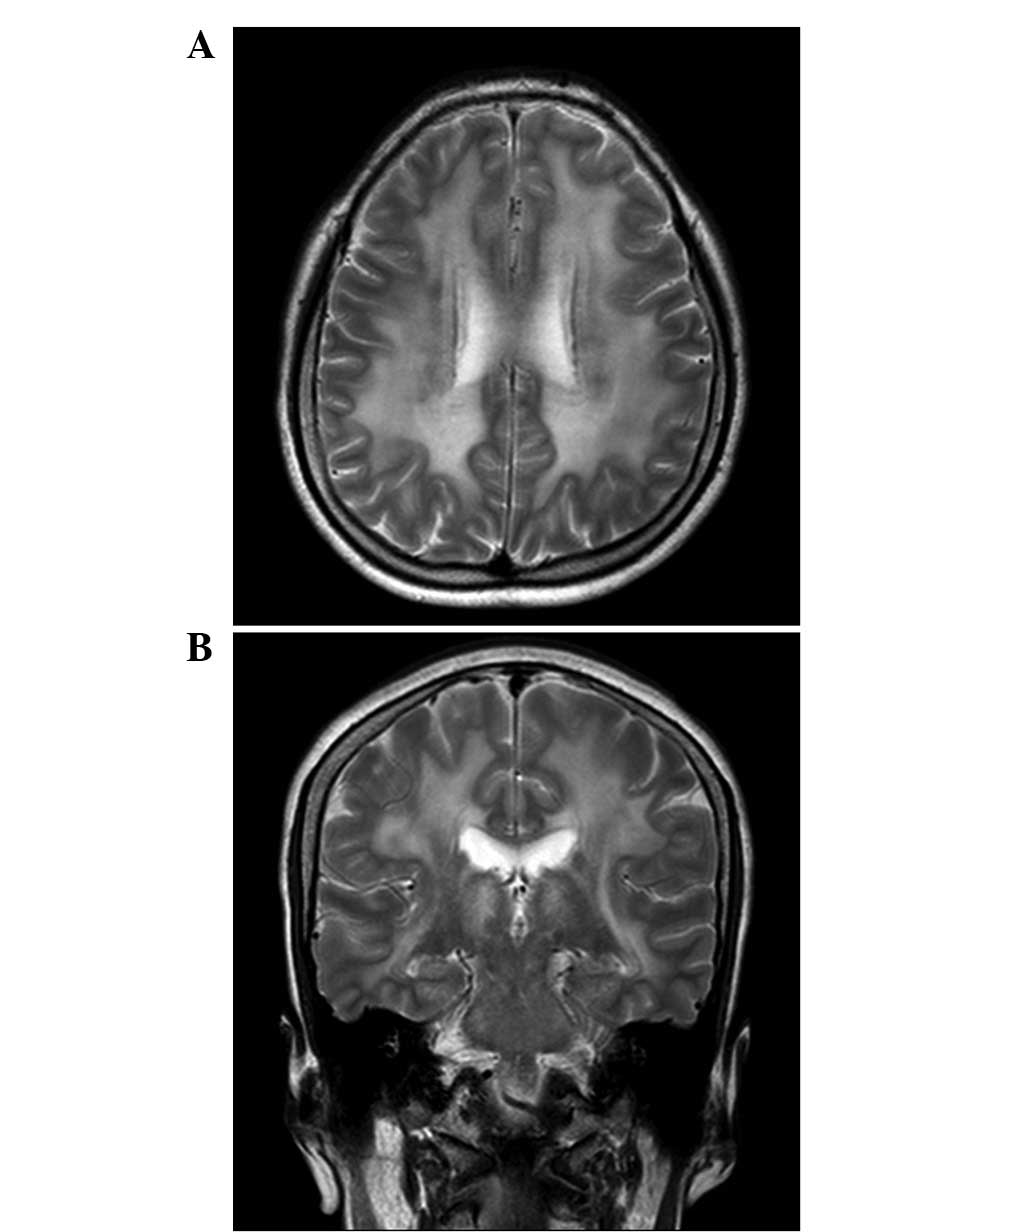

Fazekas grades. Перивентрикулярный лейкоареоз головного мозга мрт. Лейкоареоз и гидроцефалия. Перивентрикулярный лейкоареоз на кт. Перивентрикулярная лейкоэнцефалопатия мрт.

Fazekas grades. Перивентрикулярный лейкоареоз головного мозга мрт. Лейкоареоз и гидроцефалия. Перивентрикулярный лейкоареоз на кт. Перивентрикулярная лейкоэнцефалопатия мрт.